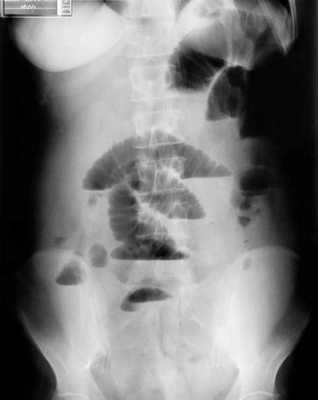

(г, д) На рентгенограммах выявлен симптом «штопора» — спиральная конфигурация 4-го отдела двенадцатиперстной кишки и проксимальной части тощей кишки.

б) Лучевая диагностика заворота тонкой кишки. При стандартной рентгенографии чаще выявляют неспецифические признаки, и она редко бывает информативной в диагностике. Симптом «штопора», известный как диагностический признак заворота средней кишки, отображает спиральную конфигурацию 4-го сегмента двенадцатиперстной кишки и проксимальной части тощей кишки, классически выявляемую при рентгенографии у детей, особенно у младенцев. Его можно визуализировать в переднезадней и боковой проекциях.

2. При завороте средней кишки определяют характерные признаки, такие как симптом «штопора» (спиральная конфигурация дистальной части двенадцатиперстной кишки и проксимальной части тощей кишки), выявляемый при рентгенографии, и симптом «водоворота» — перекручивание верхней брыжеечной вены, брыжеечного жира и кишки вокруг верхней брыжеечной артерии, выявляемый при КТ с контрастированием.